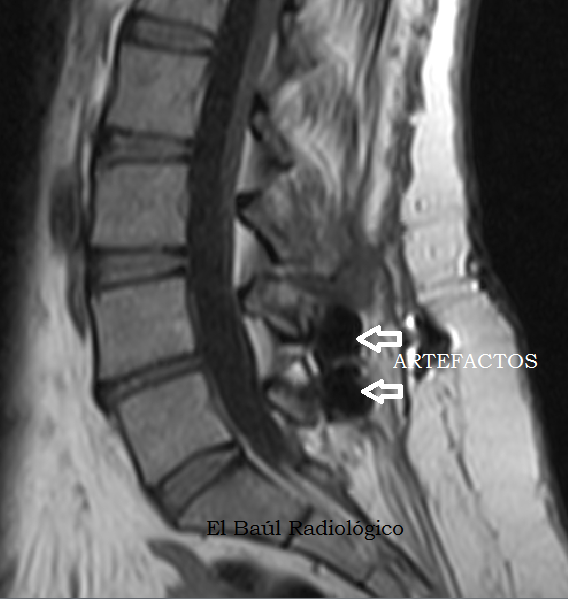

Los dispositivos más raros y variados que se suelen encontrar en cualquier imagen radiográfica, son los que utilizan los traumatólogos y neurocirujanos para estabilizar las vértebras de la columna lumbar. Como son de titanio no suelen contraindicar ninguna exploración de TRM. Tampoco se calientan, ni se mueven. En cambio, en los exámenes de TC producen numerosos artefactos radiales, como cualquier otro metal.

(The most rare and varied devices that we usually find are those used by orthopedic surgeons and neurosurgeons, to stabilize the vertebrae of the lumbar spine. Here are some very specific models of interspinous metal implants used in our hospital. Made of titanium, they not contraindicate any exploration of MRI. Neither heat, nor moved. In contrast, in CT examinations they produce many radial artifacts, like any other metal)

FIGURA 4-B) Artefactos redondeados producidos por dos implantes interespinosos.

(Rounded artifacts produced by two interspinous implants)